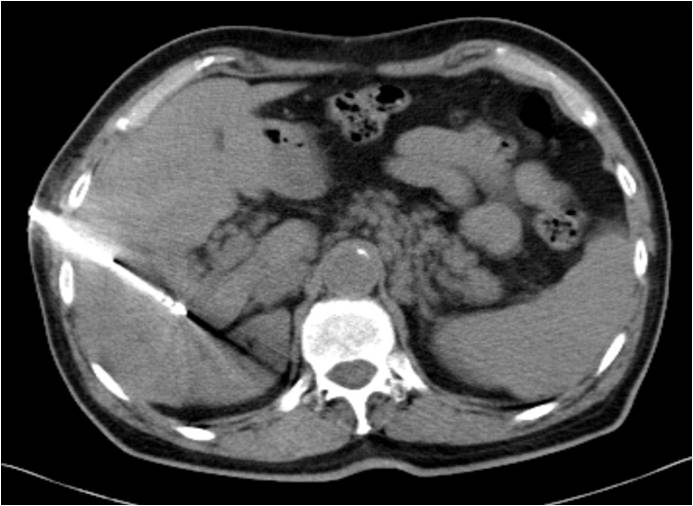

(Απεικόνιση της αντένας εντός της ηπατικής εστίας με βοήθεια Αξονικής Τομογραφίας)

Αφού προηγηθεί τοπική αναισθησία και ενδοφλέβιος φαρμακευτικός κατευνασμός του ασθενούς, τοποθετείται διαδερμικά, με την καθοδήγηση υπερήχων, ή αξονικού τομογράφου η βελόνη-ηλεκτρόδιο εντός της ηπατικής εστίας, μέσω της οποίας μεταδίδονται οι ραδιοσυχνότητες ή τα μικροκύματα. Το τελικό αποτέλεσμα κρίνεται άμεσα με την εφαρμογή της εφαρμοζόμενης απεικονιστικής μεθόδου ή σε δεύτερο χρόνο μερικές εβδομάδες αργότερα.